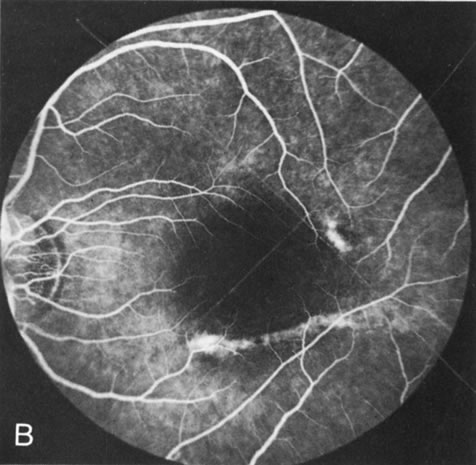

When the macula has typical superficial linear plications radiating from the fovea seen with schisis (e.g., juvenile retinoschisis, Goldmann-Favre disease), FA is normal (Fig. 8A and B). This indicates that the pathology is in the inner retina (probably Henle's fiber layer, considering the spokewheel pattern). However, when the schisis flattens, it is not uncommon to see a transmitted hyperfluorescence suggesting a secondary atrophy to the RPE (Fig. 8C and D).

Fig. 8. Juvenile XLR retinoschisis. The superficial macula schisis (A) does not affect the angiogram (B) except in a few areas where it has flattened and resulted in some pigment dispersion. When the macular schisis has entirely flattened (C) there is a mild transmission hyperfluorescence (D). At this stage the diagnosis can be suspected by the presence of an inferior retinoschisis (present in half) and confirmed by the typical electroretinographic finding of a scotopic electronegative response (present in all affected males).

The periphery may show schisis or vascular sheathing. Histopathology of the peripheral schisis in juvenile retinoschisis documents a splitting of the nerve fiber layer.13 FA shows retinal vascular abnormalities, including capillary nonperfusion, focal and diffuse vascular leakage, and intraretinal neovascularization, in many of these disorders.14 These may or may not be associated with schisis.